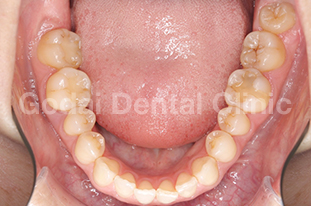

患者様は20代女性、むし歯の治療と歯並びを改善したいという主訴で来院されました。口の中を診査していくと、奥歯に装着された古い金属の下がむし歯になっていました。また下の前歯がガタガタになってきていること、前歯が出てきたことを患者様は気にしていました。むし歯については、審美性・耐久性・生体親和性を考えセラミックス治療を行い、歯並びの改善はマウスピースを用いたインビザライン矯正治療を行うことになりました。

まずはセラミックスを用いてむし歯の治療を行いました。その後、インビザライン矯正治療に移行し、約1年の移動期間で治療を終えることができました。金属を外しセラミックスで治療したことで口の中が明るくなり、矯正治療により上の前歯が出ていることと下の前歯のガタガタを改善することができました。歯並びが良くなることで将来的にむし歯と歯周病のリスクを下げることができますし、ステインも付着しにくくなるので今後のメンテナンスをやりやすくなるのが大きな魅力です。

治療前2

治療後2